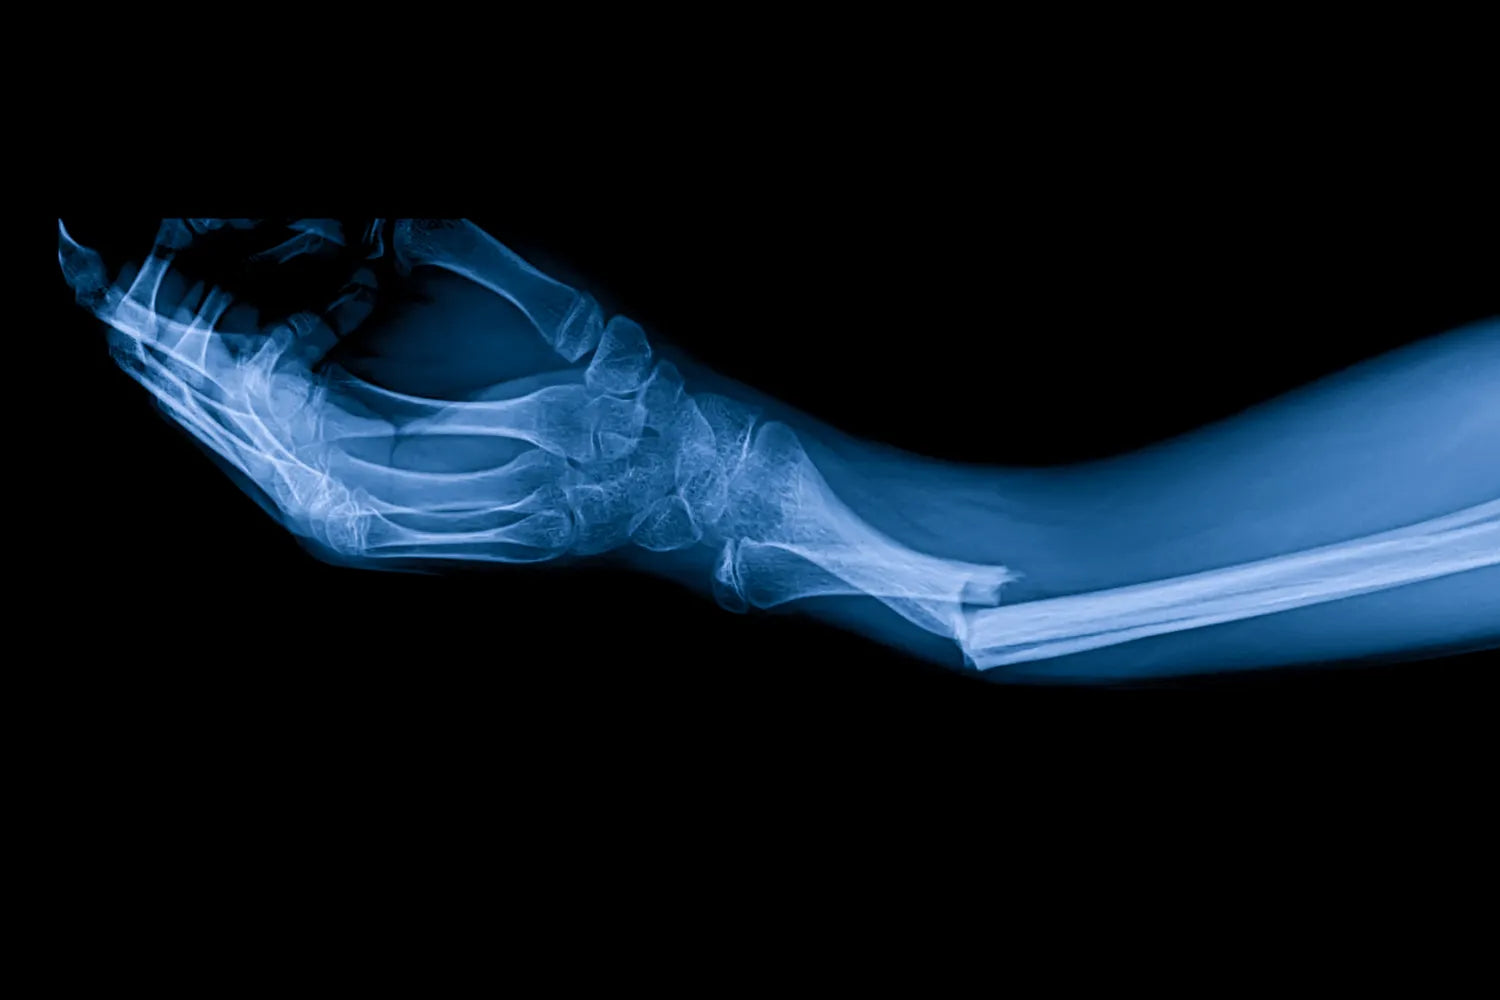

¿El colágeno ayuda a curar los huesos rotos?

Si te fracturaste un hueso, ya sabes que la recuperación puede tardar de seis a ocho semanas en promedio, a veces incluso más si te fracturaste algo como la pelvis o la tibia. Dependiendo del hueso que te hayas fracturado, eso implica mucho tiempo de inactividad, y es posible que estés deseando volver a la normalidad.

Cuando te fracturas un hueso, tu cuerpo no se limita a "reparar" y da por terminado el proceso. Es más bien como un proyecto de construcción de cuatro etapas.

Primero, se forma un hematoma (léase: moretón interno). Luego, se empieza a formar un callo blando de colágeno y cartílago. Esta solución temporal ayuda a cerrar la brecha hasta que pueda crecer tejido óseo real.

Aquí es donde el colágeno resulta realmente útil. Durante la fase fibrocartilaginosa, proporciona la estructura para que otras células (como los osteoblastos) se instalen y comiencen a formar hueso. Con el tiempo, este andamiaje se mineraliza y endurece, formando un callo óseo sólido.

El colágeno garantiza que todo sane con la forma y la fuerza adecuadas. Sin suficiente colágeno, la remodelación ósea podría tardar más, debilitarse o adoptar una forma incorrecta.